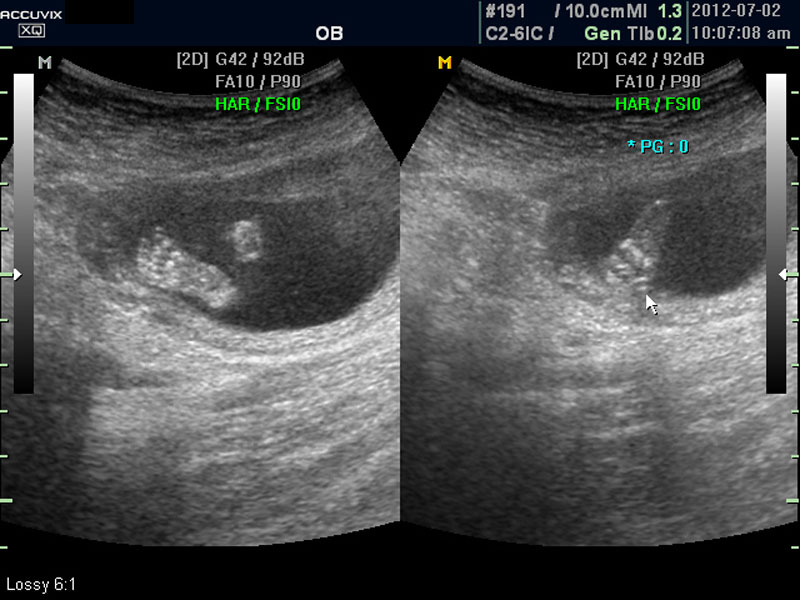

화면에서는 위쪽에 하얗게 균일하게 보이는 것이 태반의 모습입니다.

태반은 실제로 보면 피자처럼 둥그런 원판 모양이며 임신 후기로 갈수록 태아와 마찬가지로 크기가 커지고 두꺼워집니다.

양수의 양은 태아의 건강과 관련된 지표로 너무 많거나 너무 적으면 좋지 않은데 그 절대양을 측정할 수는 없어서 양수가 많은 부분의 깊이를 측정하거나 혹은 개략적으로 전체에서 차지하는 부분을 봐서 이상 여부를 판단합니다.

사진에서 검게 보이는 것이 양수입니다. 양수에 대하여는 색깔이나 밀도 등 다른 요소는 알기 어려워서 그 양만 가지고 판단을 하게 됩니다.